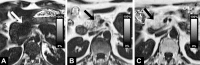

Materials and methods: From the prospective population-based Study of Health in Pomerania (SHIP), 1367 volunteers (563 men, 678 women; median age, 50 years) underwent whole-body magnetic resonance (MR) imaging at 1.5 T, which included multiecho chemical shift-encoded acquisition of the abdomen. SHIP was approved by the institutional review board, and written informed consent was obtained from all participants. The proton density fat fraction (PDFF) was calculated after correction for T1 bias, T2* bias, multipeak spectral complexity of fat, and noise bias. On the basis of oral glucose tolerance test results, participants were grouped into those with normal glucose tolerance (n = 740), those with prediabetes (n = 431), and those with confirmed type 2 diabetes but without medication (n = 70). PDFF was assessed in the pancreatic head, body, and tail. Multivariable regression analysis was conducted to investigate possible relationships of PDFF with demographic factors, behavioral factors, and laboratory data associated with the metabolic syndrome.

Results: In all subjects, the mean unadjusted pancreatic fat content was 4.4% (head, 4.6%; body, 4.9%; tail, 3.9%; being unequally distributed, P < .001). There was no significant difference in pancreatic PDFF among subjects with normal glucose tolerance, prediabetes, and type 2 diabetes (P = .980). Pancreatic PDFF showed a positive association with age and body mass index and a negative association with serum lipase activity (P < .001).